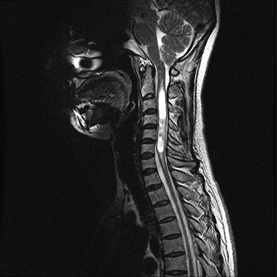

후종인대 골화증, 척추변형/기형(측만증, 후만증 등), 척추 (척추일반질환, 척추종양, 척추암, 척추전이암, 척추신경종양), 양성 및 악성 척추 종양, 경추/흉추 질환(디스크, 후종인대골화증, 황색인대골화증, 제1,2경추불안정)

양성 및 악성 척추 종양, 전이성 척추종양, 척수신경초종, 척수 공동증

후종인대골화증, 경추척수증, 척추/척추 종양

※ 중증 척추질환으로 수술이 급한 환자를 위한 "응급 중증 척추질환 심층진료"가 목요일 오후에 있습니다. 전화 예약만 가능하오니 1588-5700 으로 연락하여 주십시요. - 대상 질환: 척추/척수종양, 후종인대골화증, 척추혈관기형으로 인한 척수증 (보행장애, 상하지 위약) - 대상 환자: 조기 혹은 응급 수술이 필요하다는 내용의 진료의뢰서를 받은 날로부터 2주 이내인 경우 * 중증 질환이 아닌 요추 추간판탈출증(허리 디스크), 요추 협착증 등 퇴행성질환은 대상이 아니오니 해당질환의 수술은 연고지의 병원을 이용하여 주십시요.